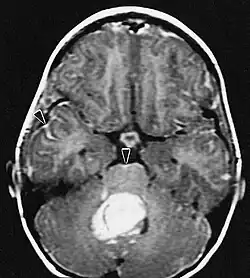

Metástase intracraniana

Existem três tipos de metástases intracranianas: metástases cerebrais, metástases durais e metástases meníngeo-leptomeníngeas. A metástase cerebral pode ser única ou múltipla e afetar qualquer parte do cérebro. A metástase para estruturas durais geralmente ocorre por disseminação hematogênica ou invasão direta de um osso adjacente. As metástases durais podem invadir o cérebro subjacente e causar edema focal e sintomas neurológicos associados. Devido à sua localização cortical, esses processos tendem a causar convulsões no início do curso. A metástase leptomeníngea é um fenômeno clínico raro, mas bem reconhecido em pacientes com câncer. As metástases leptomeníngeas são mais comumente causadas por tumores primários de mama, pulmão ou melanoma.

As metástases cerebrais são as neoplasias intracranianas mais comuns em adultos, sendo dez vezes mais comuns que os tumores cerebrais primários. Eles pisam em 20 até 40 por cento dos adultos com câncer e estão associados principalmente ao câncer de pulmão e mama e melanoma . Essas lesões resultam da disseminação de células cancerígenas pela corrente sanguínea e ocorrem mais comumente na junção da substância cinzenta e branca, onde a seção transversal dos vasos sanguíneos se altera, aprisionando embolias de células tumorais . 80 por cento das lesões ocorrem nos hemisférios cerebrais, 15 por cento no cerebelo e 5 por cento no tronco cerebral. Cerca de 80 por cento dos pacientes têm história de câncer sistêmico e 70 por cento têm múltiplas metástases cerebrais.

Avanços significativos foram feitos recentemente no diagnóstico e tratamento dessas lesões, resultando em melhora da sobrevida e controle dos sintomas. O início dos sinais e sintomas é semelhante ao de outras lesões maciças no cérebro. O método diagnóstico de escolha é a ressonância magnética com meio de contraste.